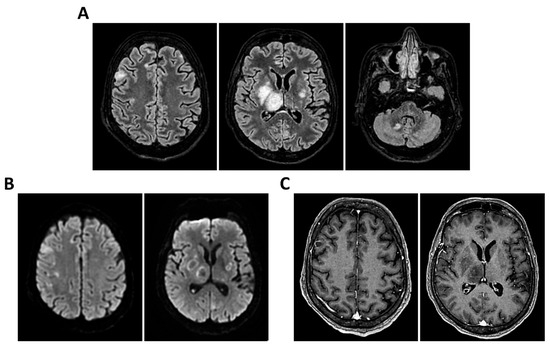

Background: Meningoencephalitis is a complex inflammatory condition of the CNS that can result in significant morbidity and mortality in critically ill adults. Accurate and timely neuromonitoring is essential for guiding management and improving outcomes. This study aimed to descriptively evaluate the prognostic value of early TCCD monitoring, particularly the pulsatility index, and its integration with conventional and perfusion MRI in patients with meningoencephalitis. Methods: We present an observational, retrospective, cohort study involving ten adult patients (median age 56 years, IQR 45.5–68.5; mean 55.9, range 35–76) with neurological syndromes caused by suspected or confirmed infectious meningoencephalitis. Etiologies included bacterial meningitis/meningoencephalitis (50%), viral meningoencephalitis (10%), neurotoxoplasmosis (10%), progressive multifocal leukoencephalopathy (10%), and undetermined origin (20%). Patients underwent TCCD and MRI within 24 h. In five cases, standard MRI sequences were acquired, while in the remaining five, perfusion imaging was performed using Arterial Spin Labelling (ASL). A favorable outcome was defined as survival with neurological recovery (Glasgow Outcome Scale > 5) at ICU discharge. Results: TCCD-derived PI provided valuable information on cerebral hemodynamics. PI values ≤ 1.25 were associated with favorable clinical outcomes and symmetrical MRI findings. Conversely, PI > 1.25 correlated with poor prognosis and often preceded MRI-detectable structural damage. When combined with ASL, PI mirrored the detected perfusion asymmetries and was associated with poor prognosis in fatal cases. Conclusions: Bedside TCCD can offer real-time assessment of cerebrovascular dynamics and, when integrated with conventional and ASL MRI, could enhance the understanding of pathophysiological processes in meningoencephalitis, supporting timely and informed decisions in neurocritical care.